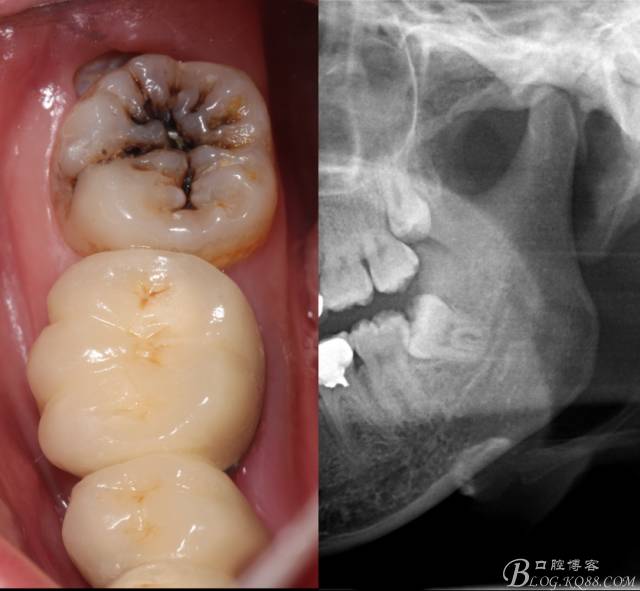

檢查:(1)37牙合面齲,卡探針. (2)38近中埋伏阻生

X全景片示38近中三類阻生,非融合根,近中根壓下頜管,37遠(yuǎn)中鄰面中齲樣影像。

先分析智齒的情況,口內(nèi)直觀是半個(gè)牙尖都沒(méi)露出來(lái),差一點(diǎn)就完全埋伏了。磨牙后墊的可操作面積中規(guī)中紀(jì),X全景片示三類阻生,根冠比例是1:1,非融合根,近中根壓下頜管。